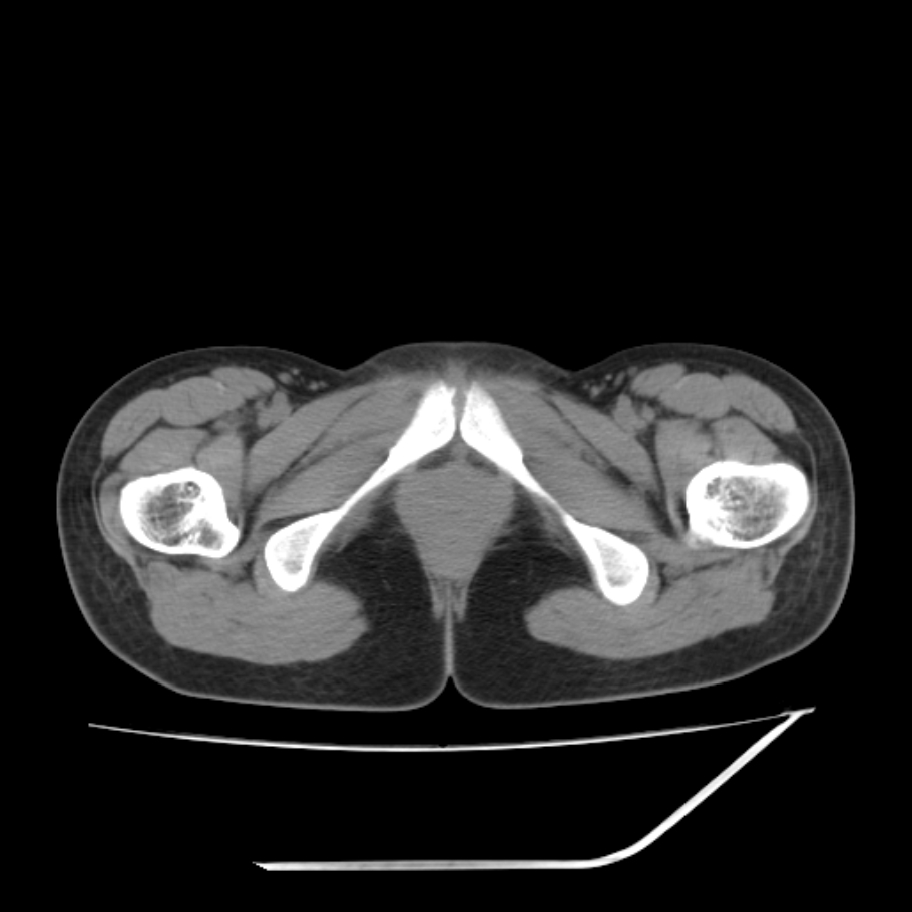

女,25岁。偶尔有右下腹不适感,余无明显异常。(结婚半年),囊壁较厚,是卵巢囊肿吗?

其上一层面见两枚小气泡影,考虑为肠管影可能,不完全除外囊肿

右侧卵巢区椭圆形囊性肿物,内壁光滑 无分隔。直肠子宫间隙内有少量积液征象。结合临床考虑卵巢巧克力囊肿,还要问问有没有痛经,本例ct怎么没有灌肠?要是灌肠或前一前口服造影剂,起码可以和肠管区别开

b超示:囊实性占位,畸胎瘤?临床有痛经。

考虑右侧卵巢囊性占位性病变(巧克力囊肿?),盆腔积液有不排除宫外孕可能,请结合临床和b超。

右侧卵巢囊伴盆腔少量积液。